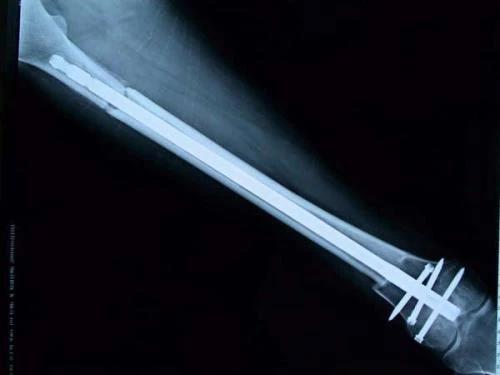

新輔助化療的目的是盡早殺滅遠(yuǎn)處微小轉(zhuǎn)移灶,縮小腫瘤及周圍炎性水腫反應(yīng)區(qū),以利于后續(xù)的保肢手術(shù);觀察腫瘤對化療的敏感性,為進(jìn)一步指定個(gè)體化的術(shù)后化療方案奠定基礎(chǔ)。骨肉瘤新輔助化療下的保肢治療如下圖所示: